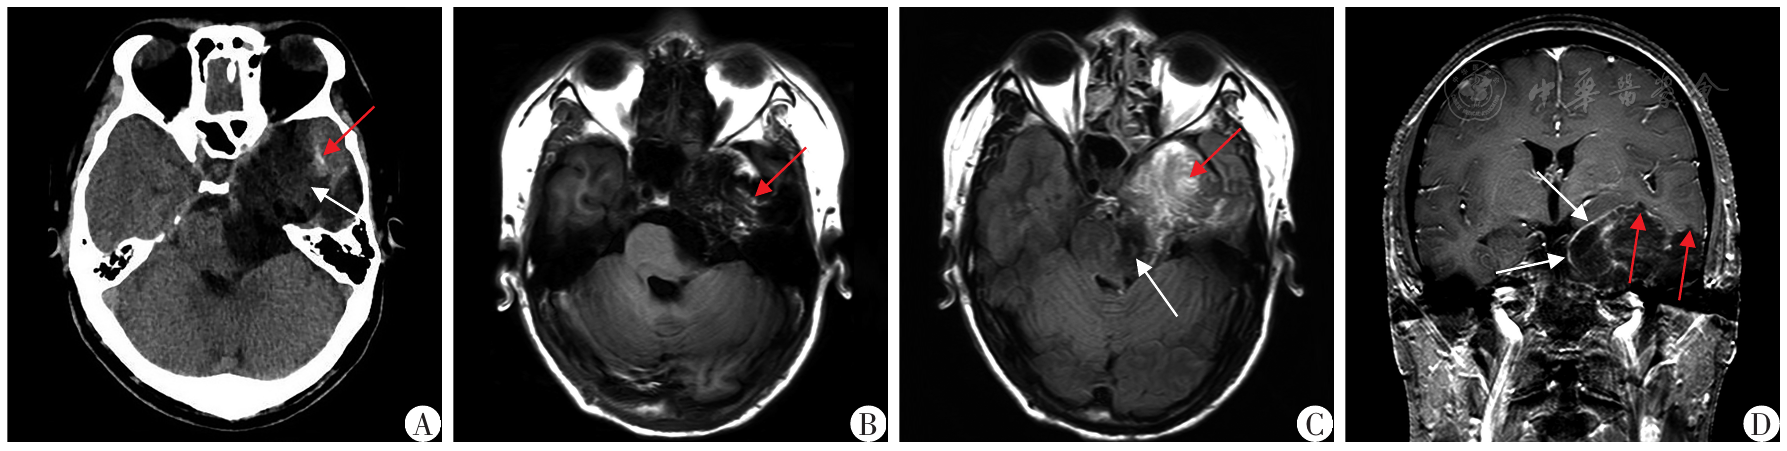

图1 左侧颞叶表皮样囊肿患者术前影像资料A:CT以低密度为主,CT值-7.9~7.7 HU,伴内部片絮状影(白色箭头所示)及边缘局部钙化(红色箭头所示);B:MRI T1WI呈低信号,伴内部漩涡状T1WI高信号(红色箭头所示);C:FLAIR信号不均匀减低(白色箭头所示),伴漩涡状改变(红色箭头所示);D:边缘轻度线样强化(白色箭头所示),与脑实质交界区虫蚀样破坏/尖角样突起(红色箭头所示)

Fig.1 Preoperative imaging data of the patient with an epidermoid cyst in the left temporal lobe